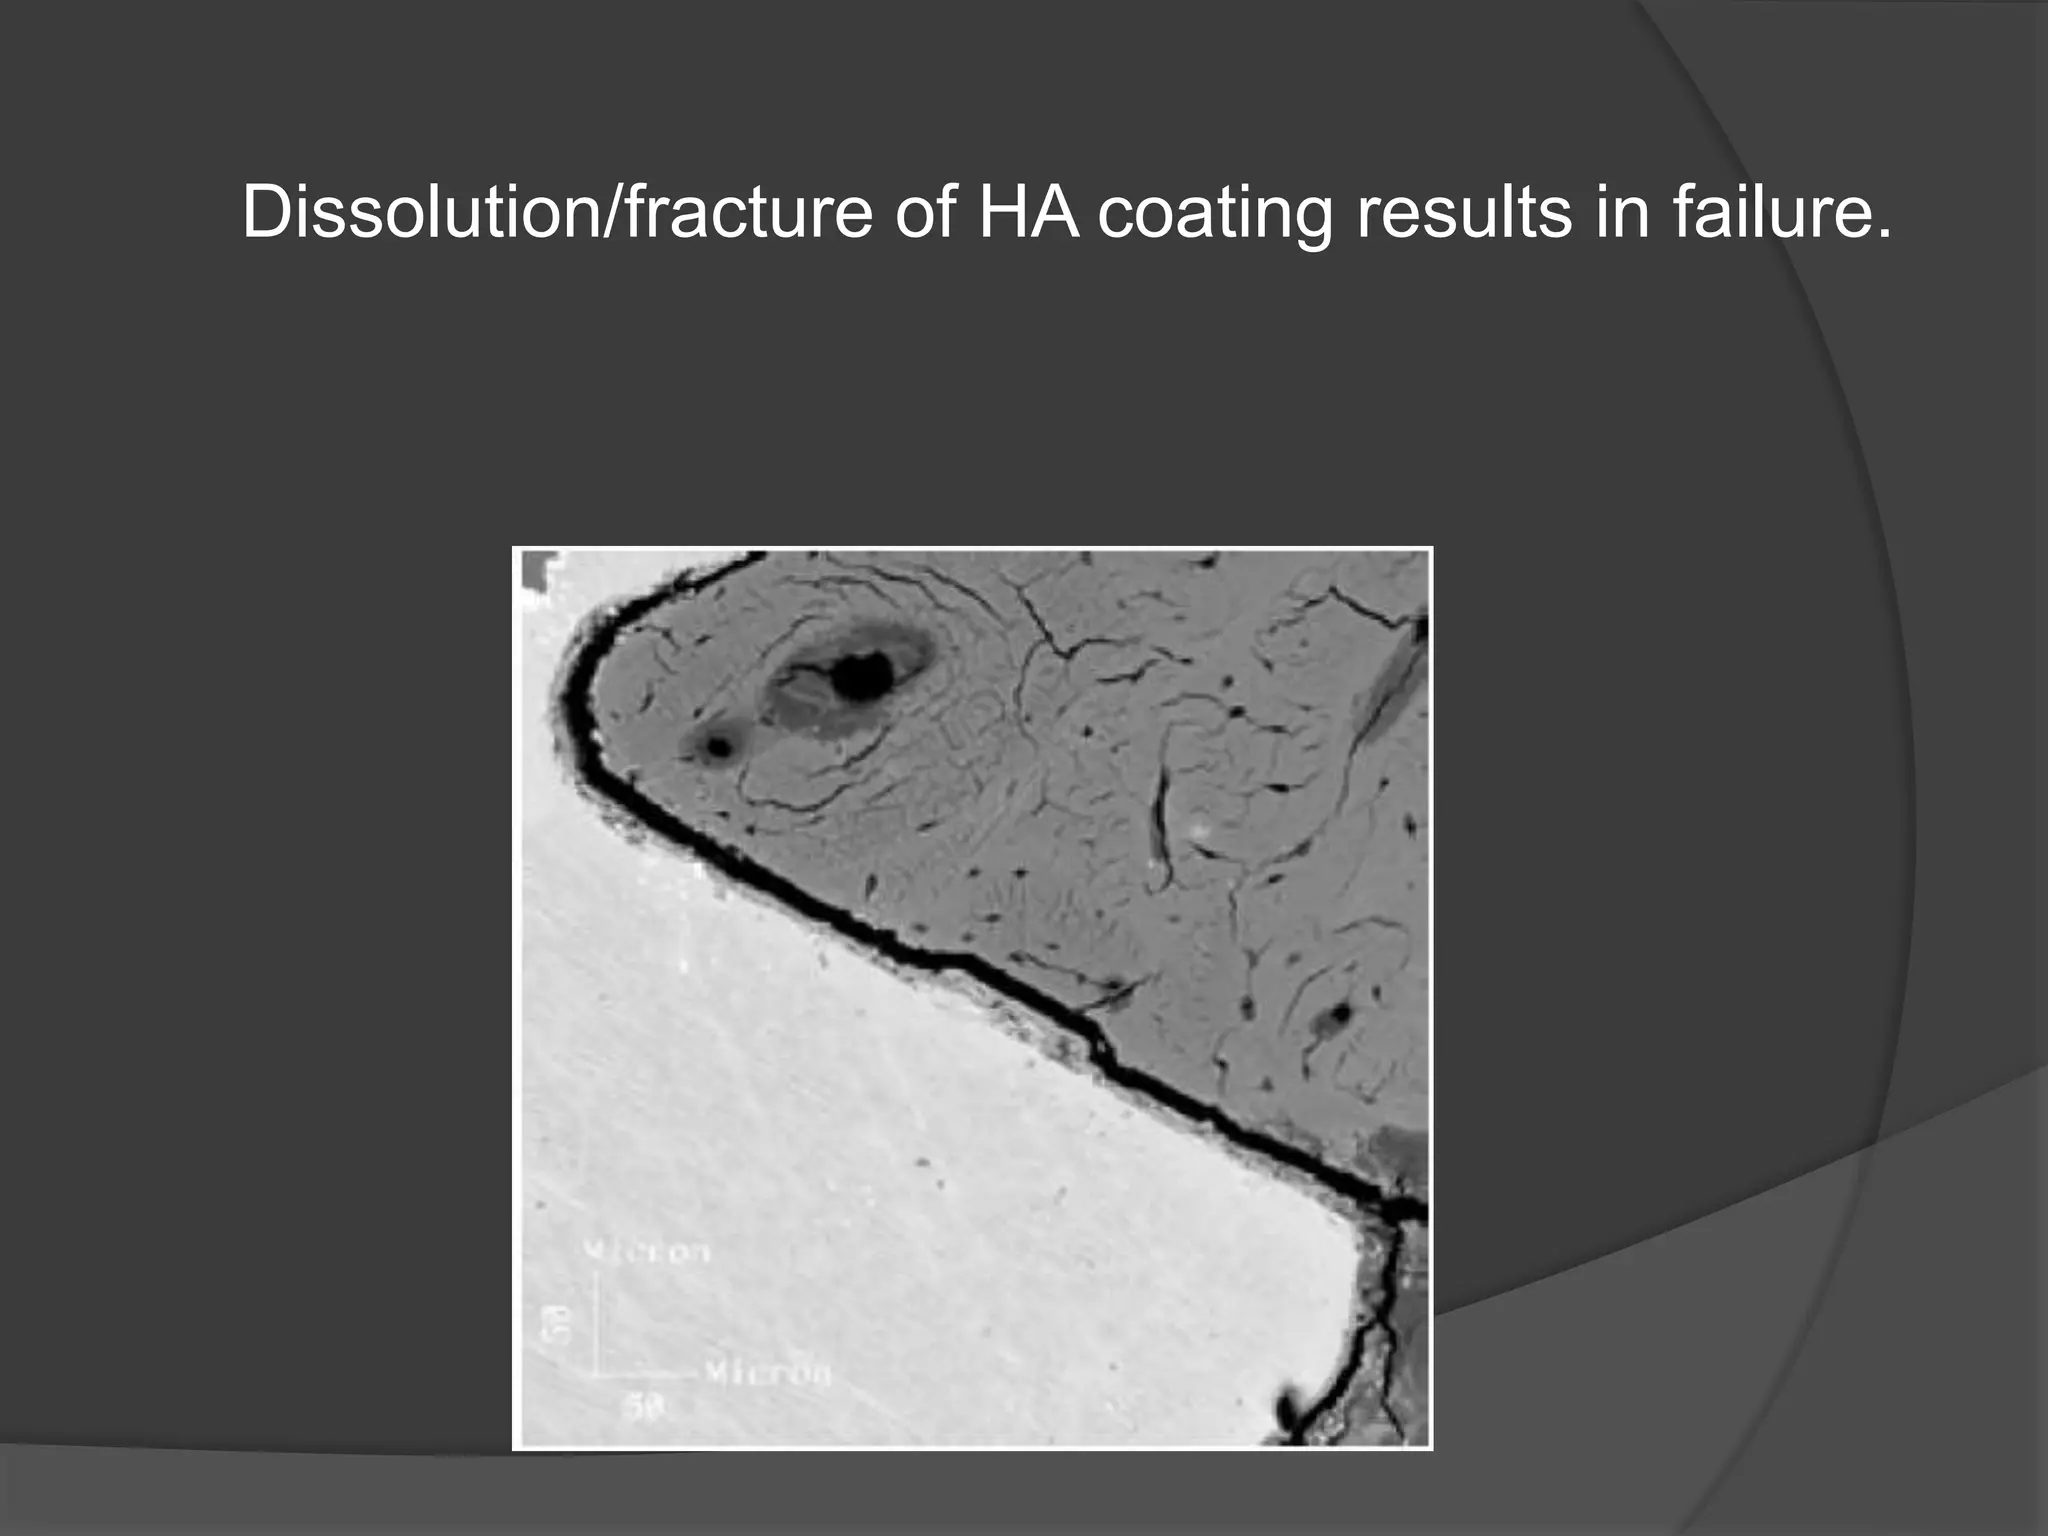

This document discusses factors that influence osseointegration and primary stability of dental implants, including implant design characteristics, surgical technique, and loading protocols. Specifically, it covers the processes of osseointegration and how forces on implants can either promote or inhibit bone remodeling. Key implant design considerations like length, diameter, threads, coatings and surface topography are analyzed in terms of their effects on stress distribution and bone-implant contact. The importance of primary stability and factors influencing it like bone quality and surgical skill are also addressed. Loading protocols ranging from immediate to conventional loading are compared.